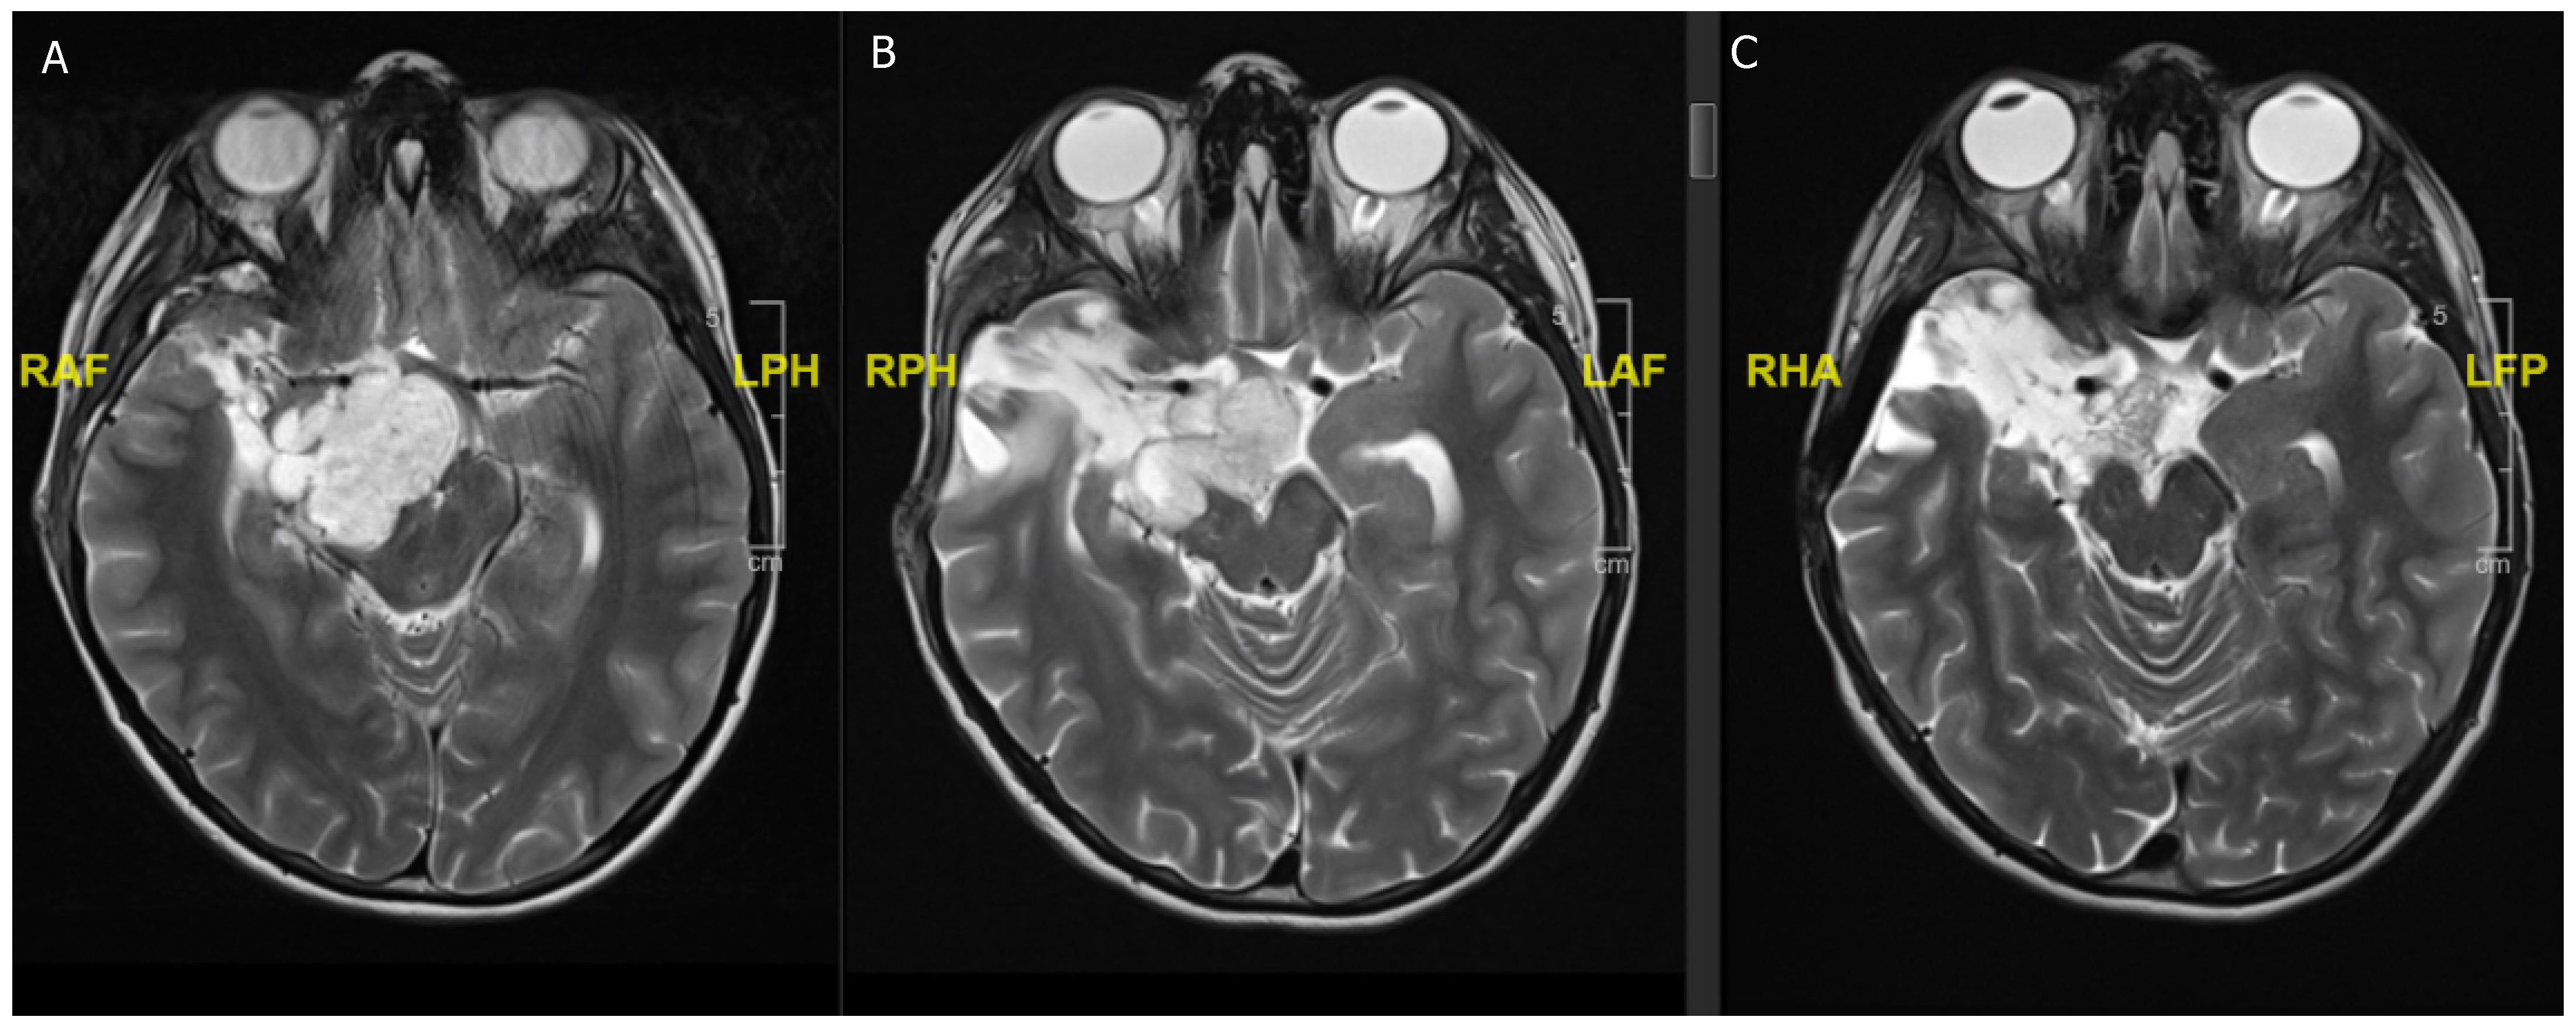

Figure 2. A 16-year-old girl previously diagnosed with TSC and presenting with acute headaches and vomiting. (A) Acute obstructive hydrocephalus and edema due to T2 hypointense lesion in the right frontal horn. (B) Contrast enhancing lesion in the right frontal horn suggestive of SEGA in the context of TSC. (C) Postoperative scan with reduction of ventricular size and showing complete resection of the SEGA.

3.2. Tuberous Sclerosis Complex

The TSC negatively regulates the mTOR pathway, resulting in typical subependymal giant cell astrocytoma (SEGA) in 20% of all patients, and only a small number of reports of SEGA without the clinical features of TSC exist (Figure 2) [31,32]. These tumors mostly occur in children and young adults and are unlikely to occur in adulthood [30]. If they increase in size, they can cause seizures or obstructive hydrocephalus, which is when surgical excision is recommended, although some reports showed that mTOR inhibitors are sufficient for hydrocephalus treatment as well as seizure reduction and control [9]. Moreover, preoperative treatment with mTOR inhibitors can reduce the vascularity of SEGAs, which is beneficial for surgical resection [33,34]. In most cases, the tumor can be medically treated with mTOR inhibitors, which can prevent disease progression in children >3 years of age and has also been shown to be effective terms of cognition, development, and seizure control in TSC children [34,35,36].